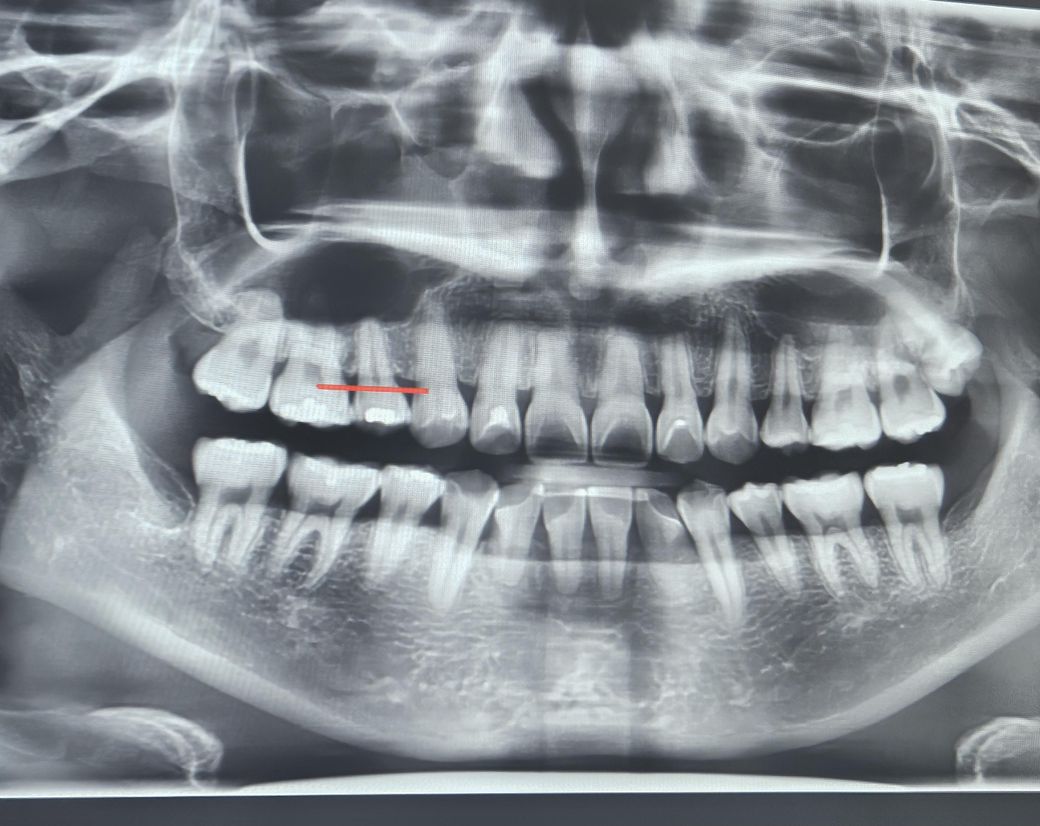

치근흡수 앞니 치아뿌리 상태 봐주세요ㅠㅠ

사랑니 뽑느라 치과에 갔는데 원장님에서 치아 뿌리가 짧다고 하셔서요. 제가 봐도 아래 앞니가 많이 짧아 보이는데ㅠㅠ 치간칫솔 등 사용하고 앞니 안쓰려고 하고 잇몸관리 하고 있습니다만ㅠㅠ 이경우 40까지 버틸 순 있을까요?

1. 교정 후 치근흡수는 흔히 발생할 수 있는 부작용이며 선천적으로 치아 뿌리가 짧은 경우도 있습니다.

2. 치근이 짧다고 해서 당장 어떤 문제가 생기거나 하는건 아니나 잇몸뼈가 노화로 퇴축되었을 때 남들보다 치아가 더 빨리 흔들리거나 할 순 있습니다.

3. 현재 치관:치근 비율로는 치아가 많이 흔들리거나 하진 않을 것입니다. 손으로 잡고 흔들어봤을때 살짝 흔들리는 정도는 생리적 동요도의 범주일 것으로 예상됩니다.